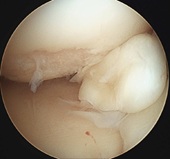

変形性膝関節症に対する関節鏡視下手術(図1)や人工関節置換術(図2)を行っています。また水曜、木曜には足の外科専門医である久保田医師が外来診療を行っており、外反母趾などの足部変形に対する専門的診察を受けることができます。

図1:半月板が損傷し関節内にひっかかっている。

図1:これを切除した。